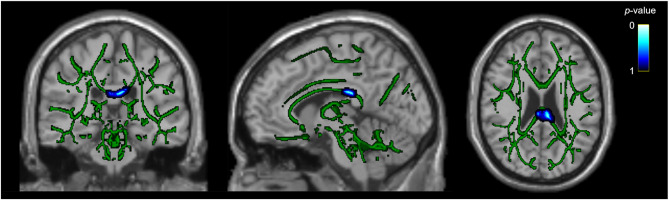

White matter tract differences in persistent post-traumatic headache, migraine, and healthy controls: a diffusion tensor imaging study.